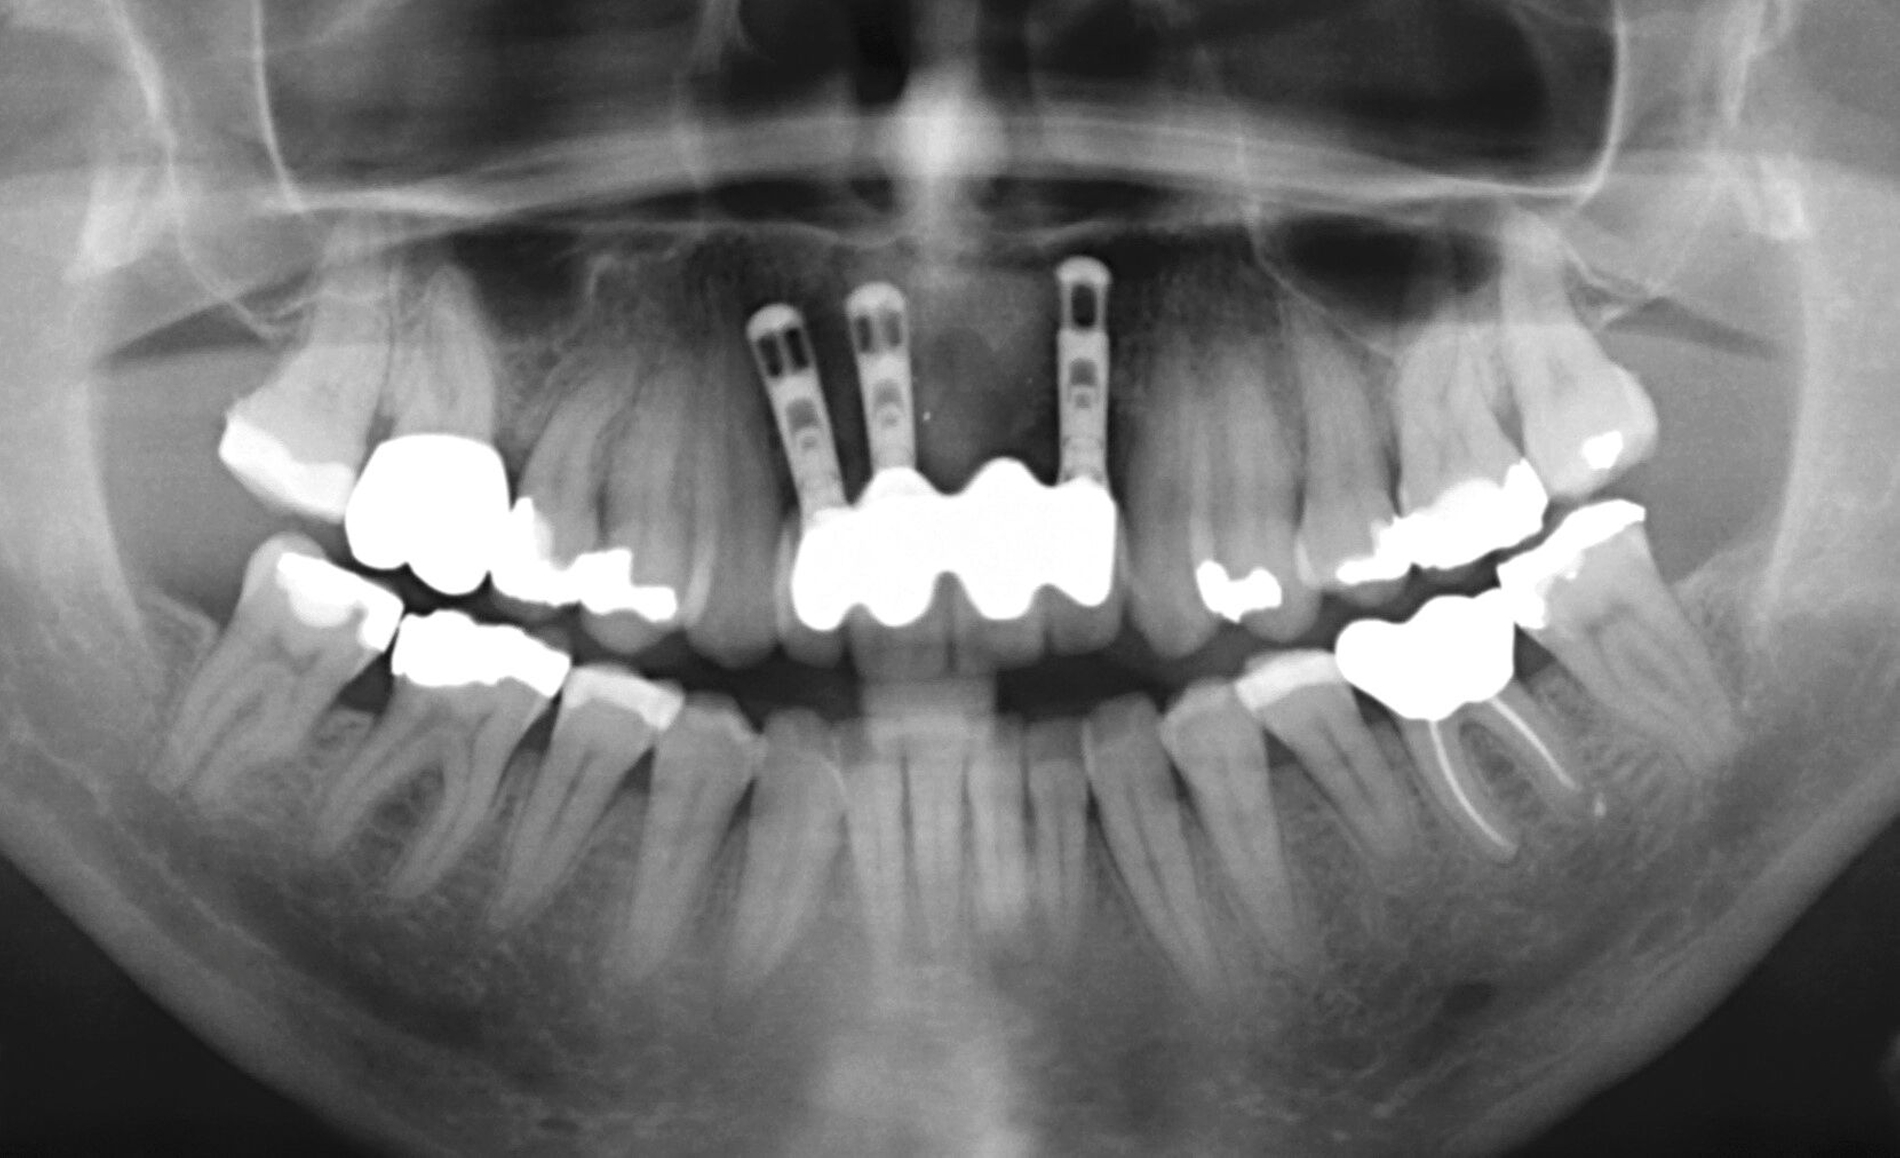

Nachdem der Patient bei einem Berufsunfall mit Ausnahme der zweiten Molaren und der Weisheitszähne alle Zähne im Unterkiefer verloren hatte, erfolgte 1996 im Alter von 44 Jahren die definitive Lückenversorgung. Hierzu wurden eine verschraubte Brückenkonstruktion (044-034-043-044) sowie zwei verblockte Kronenpaare auf insgesamt acht Implantaten eingesetzt. Nach sieben Jahren Tragedauer wurde an mehreren Implantaten röntgenologisch ein Knochenabbau festgestellt. Verkürzte Kontrollintervalle mit professionellen Zahnreinigungen und intensiven Instruktionen zur Interdentalhygiene konnten nicht verhindern, dass nach weiteren sieben Jahren Anfang 2011 der Knochenverlust an den meisten Implantaten auf 50 bis 80 Prozent zunahm (Abb. 1a).

Die Entscheidung zur Explantation fiel wegen des beschleunigten Knochenverlusts und der extrem erschwerten Bedingungen für eine effektive Mundhygiene im Bereich der Implantate mit Sondierungstiefen bis zu 12 mm (Abb. 1b und 1c). Unter Lokalanästhesie wurden sieben der acht Implantate mit einem passenden Trepanbohrer mit 0,1 mm Aufmaß im Vergleich zum Außendurchmesser der Implantate umbohrt, anschließend mit einem kleinen Rasparatorium gelockert und dann mit einer Arterienklemme entfernt. Entscheidend für die Eignung der Trepanbohrer war die Längenmarkierung, um eine Nervverletzung bei der Entfernung der sehr tief gesetzten Seitenzahnimplantate zu vermeiden (Abb. 1d und 1e). Eine ausgedehnte Lappenbildung konnte durch dieses Vorgehen vermieden werden.

Ursprünglich waren bei dieser Patientin nach einem Frontzahntrauma vier Implantat-gestützte Kronen geplant. Nach dem frühen Verlust des Implantats in regio 21 während der Einheilzeit wurde dann eine auf drei Implantaten abgestützte Brücke eingegliedert. Das bestehende vertikale und horizontale Weichgewebsdefizit wurde bei der verschraubten Implantatbrücke durch aufgebrannte rosafarbene Keramik kaschiert (Abb. 3a). Funktionell war die Brückenversorgung über viele Jahre erfolgreich und zeigte keinerlei Lockerungsgrad. Trotz guter Mundhygiene war in Kontrollsitzungen ein kontinuierlicher Knochenabbau an allen Implantaten festzustellen (Abb. 3b). Zur Vermeidung eines weiteren Knochenverlusts fiel circa 15 Jahre nach der Erstversorgung die Entscheidung zur Explantation. Zu diesem Zeitpunkt war die Patientin 55 Jahre alt.

Da sechs Monate nach der Explantation keine nennenswerte knöcherne Regeneration festzustellen war, wurde eine zweizeitige Implantation nach Knochenaugmentation mithilfe dünner Knochenscheiben aus dem Kieferwinkel geplant. Die Entnahme erfolgte mit oszillierenden Instrumenten (Piezosurgery). Der Knochenblock wurde in dünne Scheiben geschnitten und mit Osteosyntheseschrauben am Alveolarfortsatz fixiert (Abb. 3e). Darüber wurden die Weichgewebe dicht vernäht. Weitere fünf Monate später erfolgte die Schraubenentfernung und die Implantation von zwei Bone-Level-Implantaten in regio 12 und 22 mit geschlossener Einheilung (Abb. 3f und 3g). Bei der Implantatfreilegung weitere sechs Monate später wurden die Weichgewebsdefizite im Brückengliedbereich durch ein kombiniertes Bindegewebs-/Schleimhauttransplantat aufgefüllt und gleichzeitig die keratinisierte periimplantäre Gingiva und Alveloarmukosa verbreitert (Abb. 3h und 3i). Die prothetische Versorgung erfolgte erst weitere drei Monate später, nach dem Konsolidieren der Weichgewebe. Die umfangreichen Augmentationsmaßnahmen konnten das transversale Weichgewebsdefizit vollständig kompensieren, während das verbleibende vertikale Defizit zu zervikal etwas längeren Kronen und Brückengliedern führte. Aufgrund der guten Abdeckung durch die Oberlippe kann das ästhetische Ergebnis als zufriedenstellend bewertet werden (Abb. 3j bis 3l).